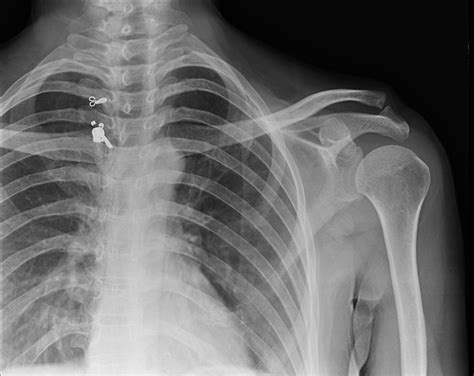

Anterior-Posterior (AP) View

The AP view is the most common and provides a frontal view of the shoulder. It is useful for assessing the glenohumeral joint, humeral head, and proximal humerus. This view helps identify fractures, dislocations, and degenerative changes in the shoulder joint.